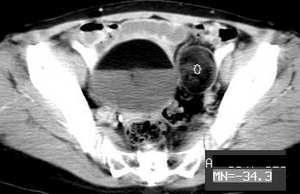

女,55岁,因下腹胀痛2月,b超发现盆腔包块7天,而入院,检查:右侧附件如女拳头大小包块,活动差,轻压痛,质中,子宫稍正常缩小,彩超示子宫4.9cmx2.6cmx2.3cm ,右侧附件包块示:8.7cmx9.1cmx6.3cm 的混合性回声,脂质分层征

囊性畸胎瘤的液-液征,增强瘤结节强化。

畸胎瘤伴瘤内出血。

请问各位高手,右侧肿块前壁的带状软组织密度是否肿瘤组织成分?

畸胎瘤,可见典型脂肪-液体征象。

同意大家畸胎瘤的诊断,但不能排除恶变的可能.

右侧肿块前壁的带状软组织密度影我认为是肠管所致,该部位的小肠肠襻由于受到肿瘤的推移呈水平样排列,这样在ct扫描时相邻的肠壁在某些层面上可以呈现宽带状软组织密度影。

良性畸胎瘤伴出血。

畸胎瘤,脂-液分层